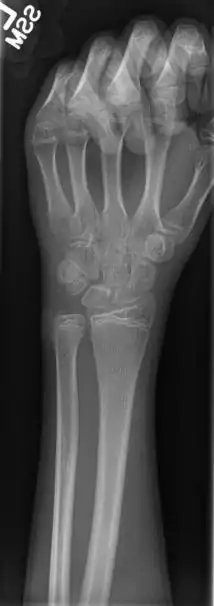

При рентгенографії пучок рентгенівського випромінювання направляють на досліджувану частину тіла; Х промені, що проникли через тіло хворого, попадають на плівку. Рентгенівська плівка має чутливість не тільки до рентгенівського випромінювання, але і до видимого світла. Тому її поміщають у касету, що захищає від видимого світла, але проникне для Х променів. Зображення на плівці стає видимим після фотообробки (прояв, фіксування). Готовий висушений знімок розглядають на світлі або на негатоскопі. Знімок будь-якої частини тіла встановлюють на негатоскопі в такому положенні, у якому лікар досліджував би дану частину тіла у хворого.

Метод рентгенографії відрізняється великими перевагами. Він простий і необтяжливий для хворого. Знімки можна робити як у рентгенівському кабінеті, так і безпосередньо в операційній, перев'язочній, або навіть у палаті (за допомогою пересувних рентгенівських установок). На знімках виходить чітке зображення більшості органів. Деякі з них, наприклад кістки, легені, серце, добре помітні завдяки природній контрастності. Інші органи ясно відображаються на знімках після їх штучного контрастування. Знімок є документом, що може зберігатися довгий час. Його можуть розглядати багато фахівців і порівнювати з попередніми і наступними рентгенограмами, тобто вивчати хвороби в динаміці.

Проведення рентгенографії вимагає дотримання визначених правил. Знімки кожного органа в більшості випадків повинні бути зроблені в двох взаємно перпендикулярних проєкціях, зазвичай використовують пряму і бічну проєкції. Знімки в двох взаємно перпендикулярних проєкціях дозволяють, крім того, визначати топографоанатомічні співвідношення органів.

При рентгенографії прагнуть максимально наблизити досліджувану частину тіла до касети з плівкою. Тоді зображення є найбільш чітким і за розмірами мало відрізняється від справжньої величини досліджуваного органа. Але існує методика рентгенографії, при якій об'єкт, що досліджується, навпаки, поміщають порівняно далеко від плівки. У цих умовах через розбіжний характер пучка рентгенівського випромінювання виходить збільшене зображення органа. Такий спосіб зйомки одержав назву рентгенографії з прямим збільшенням зображення. Він здійсненний тільки при наявності особливих «гострофокусних» рентгенівських трубок і застосовується для вивчення дрібних деталей (маленьких вогнищ і судин невеликого калібру в легенях, окремих кісткових балок і трабекул тощо).

Розрізняють оглядові і прицільні рентгенограми. На оглядових одержують зображення частини ділянки тіла (грудна клітка, живіт тощо). А на прицільних знімках відображена окрема частина органа, що цікавить лікаря, причому в оптимальній проєкції, необхідній для виявлення визначених деталей.